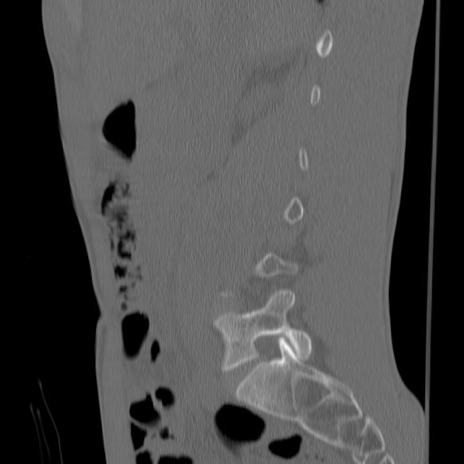

症例3 腰椎CT(矢状断像)

腰椎CT

冠状断像